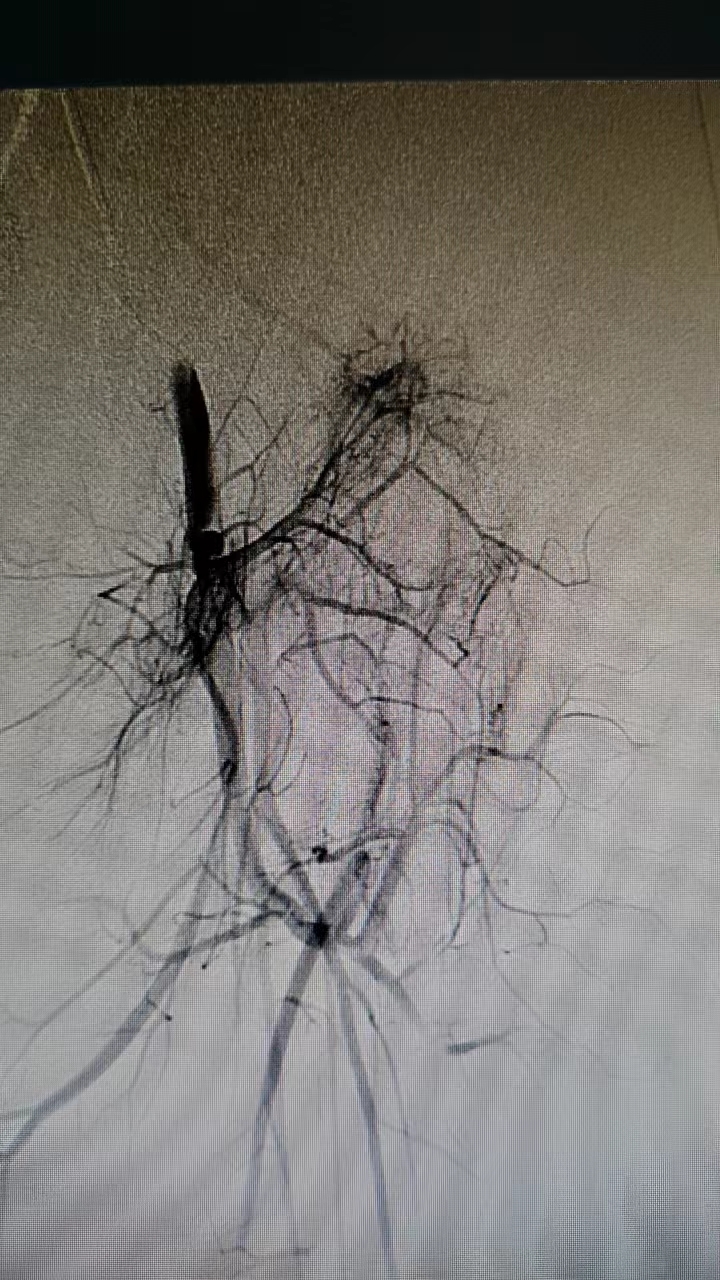

在完善下肢磁共振、血管造影等检查后,诊断更加明确。血管造影看到,可可左腿血管有多发畸形,动脉和静脉之间有异常通道连通,一部分血液在循环过程中“偷懒”走了捷径,这导致肢体各组织间营养供给不均匀,这也是可可双腿长短和粗细不一的原因。

刘新献表示,目前此病不能完全治愈,但可以通过微创介入治疗控制病情进展,尽可能的缩小差异,减轻症状。由于患儿血管较杂乱、纤细、走形迂曲,难度较大,幸运的是,在团队协作下,成功用头发丝细的导管将动静脉之间的“漏洞”分次逐步栓塞。两年间,经历三次手术后,可可的病情得以控制,双腿不等长的差距不再增长,左腿腿围缩小,红斑皮温也明显降低。